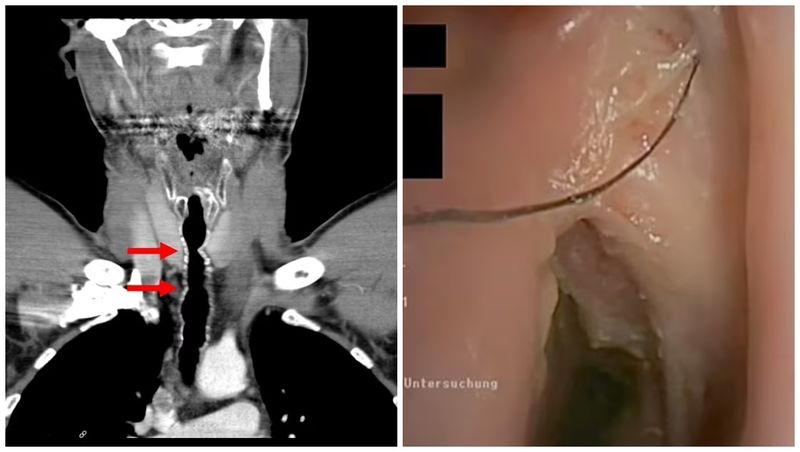

După ce au aflat ce simptome are, medicii au efectuat o procedură care le-a permis să introducă o cameră video de mici dimensiuni pe căile respiratorii ale pacientului și au descoperit că acestuia îi crescuseră mai multe fire de păr într-o zonă din gâtul lui pe care acesta suferise anterior o operație.

Bărbatul, originar din Austria, a fost diagnosticat cu creșterea părului endotraheal, sau creșterea părului în gât.

La fiecare control medical, în gâtul omului se regăseau șase până la nouă fire de păr de aproximativ 5 centimetri, unele reușind să treacă prin cutia vocală și să-i treacă în gură.

Ulterior, această secțiune în trahee a fost închisă folosind cartilaj și piele de la ureche. În zona operată i-a apărut păr în gât care a continuat să apară an de an până când pacientul s-a lăsat de fumat.